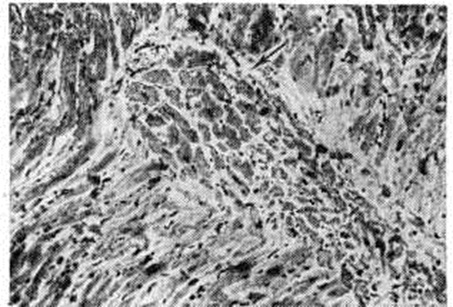

В заключительной стадии поражены обширные участки миокарда обоих желудочков, особенно — левого. В основном выявляются дистрофические и некротические изменения миокардиоцитов, начиная от вакуолизации перинуклеарной зоны цитоплазмы (смотри полный свод знаний Вакуолизация) и до цитолиза (рисунок 2) с полным растворением тел клеток (смотри полный свод знаний Цитолиз). От клеток остаются только следы в виде мелких зёрен липофусцина. В результате образуются ареактивные участки депаренхимизации миокарда (рисунок 3) с так называемой пустой сеткой, в дальнейшем замещаемые соединительной тканью. Ряд мышечных волокон подвергается мелкоглыбчатому и мелкозернистому распаду с образованием фуксинофильного детрита, резорбция которого также заканчивается миофиброзом. Процесс вакуолизации и лизиса распространяется и на клетки эндотелия кровеносных сосудов в очагах поражения. Процесс в целом напоминает дистрофический (деструктивный) миокардит. Нередко обнаруживаются также воспалительные лимфогистиоцитарные инфильтраты с примесью сегментоядерных лейкоцитов; в сочетании с дистрофическими изменениями создаётся картина смешанной формы идиопатического (аллергического) миокардита. Внутриорганные мелкие артерии и артериолы изменяются по типу аллергического васкулита (смотри полный свод знаний) — от фибриноидного некроза стенки (рисунок 4) до облитерирующего панваскулита. Все эти процессы обнаруживаются на фоне распространённых полей кардиосклероза различной зрелости (рисунок 5), подобно миокардитическому кардиосклерозу (смотри полный свод знаний Кардиосклероз), что свидетельствует о прогрессирующем и длительном течении поражения миокарда. В дистрофический и рубцовый процессы вовлечены и различные отделы проводящей системы с миоцитолизом (рисунок 6).

Рис. 2. | ||

Рис. 3. | ||